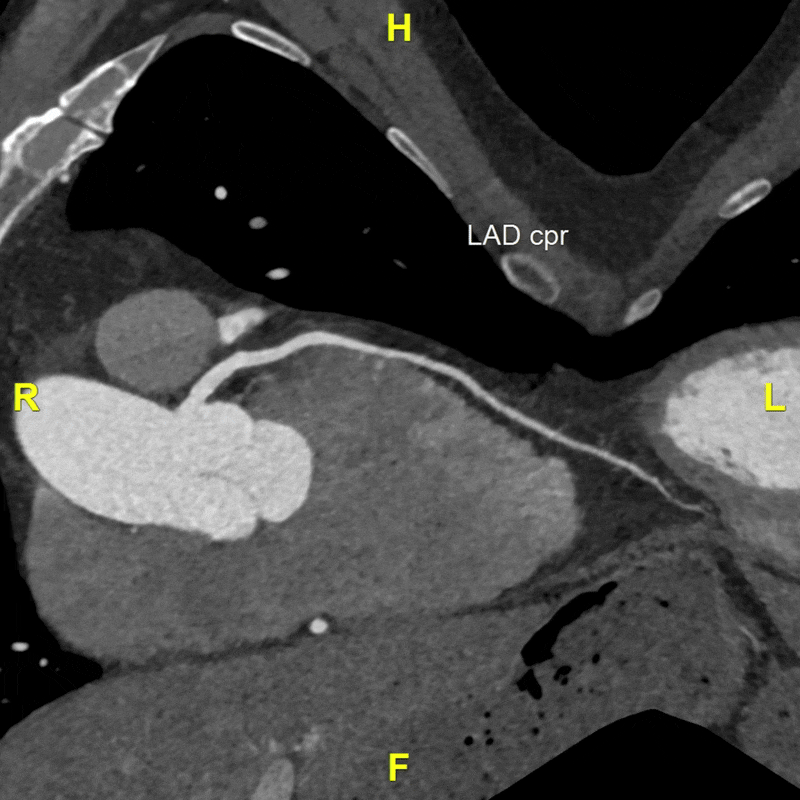

A 3DQ Lab technologist processed the scan using our aortic surveillance protocol. Standardized measurements were taken at set locations along the aorta to ensure consistency with prior studies. Volume-rendered images were generated to visualize the morphology of the aorta and its branch vessels in three dimensions. Curved planar reformats of the coronary arteries were also created to assess their course and relationship to the aortic anatomy. All measurements were then added to the patient’s graph alongside those from previous visits, demonstrating how the size of the aorta has changed over time. Below are the images provided to the Cardiothoracic Surgery team.

Figure H: Curved planar reformats (CPRs) showing the course of the coronary arteries and their relationship to the thoracic aorta. (Learn more about CPRs here).